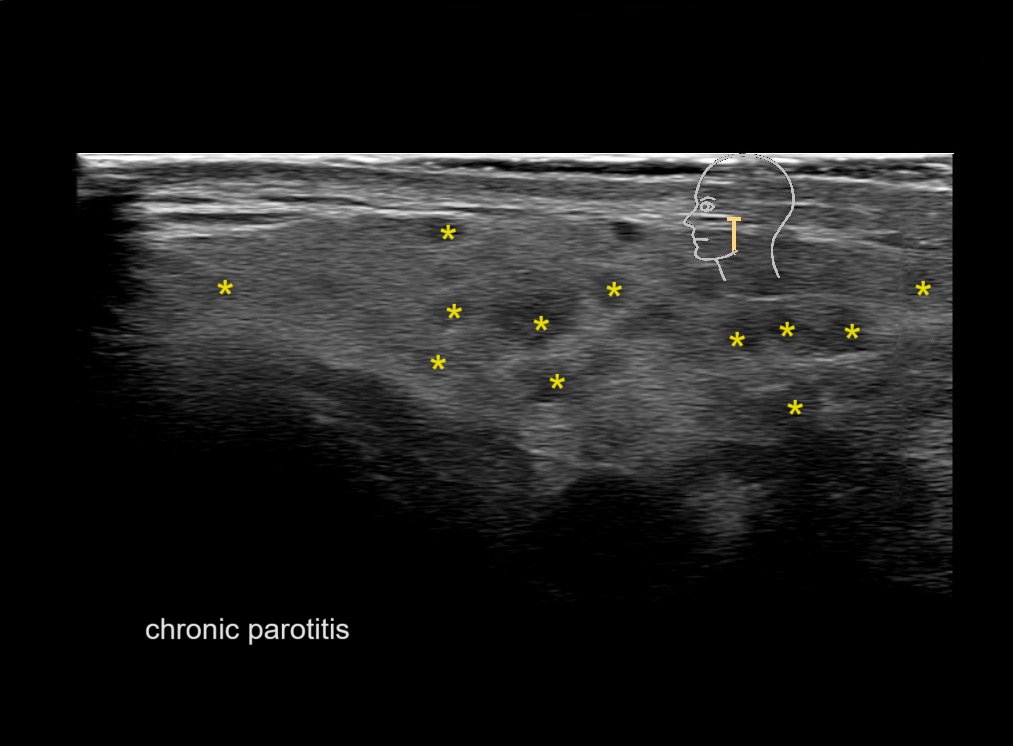

Filler injections in the parotid gland may go unnoticed, however, inflammatory reactions and abscesses may occur. Hypervascularity can be seen with color doppler. Filler deposits are supposed to be injected into the superficial fatty layer . The space to inject into this layer may be limited. Routinely we measure a width of 2-4 millimeters with sometimes subcutaneous layers being less than one millimeter thick.

Hover over an image to view the secondary image or click on the image title for more information.